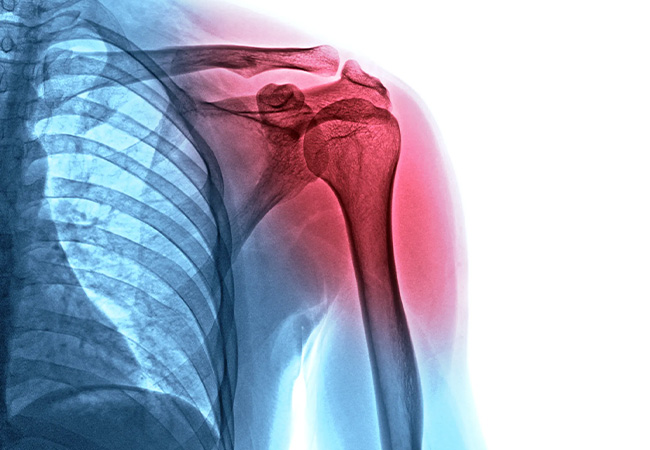

Understanding Shoulder Injuries

Sports-related shoulder injuries in indoor sports fall into two categories: overuse and acute. Understanding the difference between these types of injuries can help ensure you get timely treatment.

Overuse injuries are more common–and also more likely to be overlooked. They occur gradually due to repetitive arm motions that strain the muscles, tendons, and ligaments over time, leading to persistent pain in your shoulder or arm.

When most people hear the word “injury, ” they’re thinking of acute injuries. These injuries happen suddenly, often from a fall or collision–a shoulder dislocation is a good example. They require immediate attention to avoid long-term complications, and you’ll generally need to undergo rehabilitation to regain function.

Overuse injuries are much more common in indoor sports, as most of these sports require repetitive swinging or overhead motions (e.g., swinging a racket or shooting a basketball). These injuries generally cause pain during activities, and many athletes are tempted to ignore the pain, thinking it’ll get better on its own. In reality, that pain is usually a sign of an underlying injury that requires attention from one of our physical therapists.